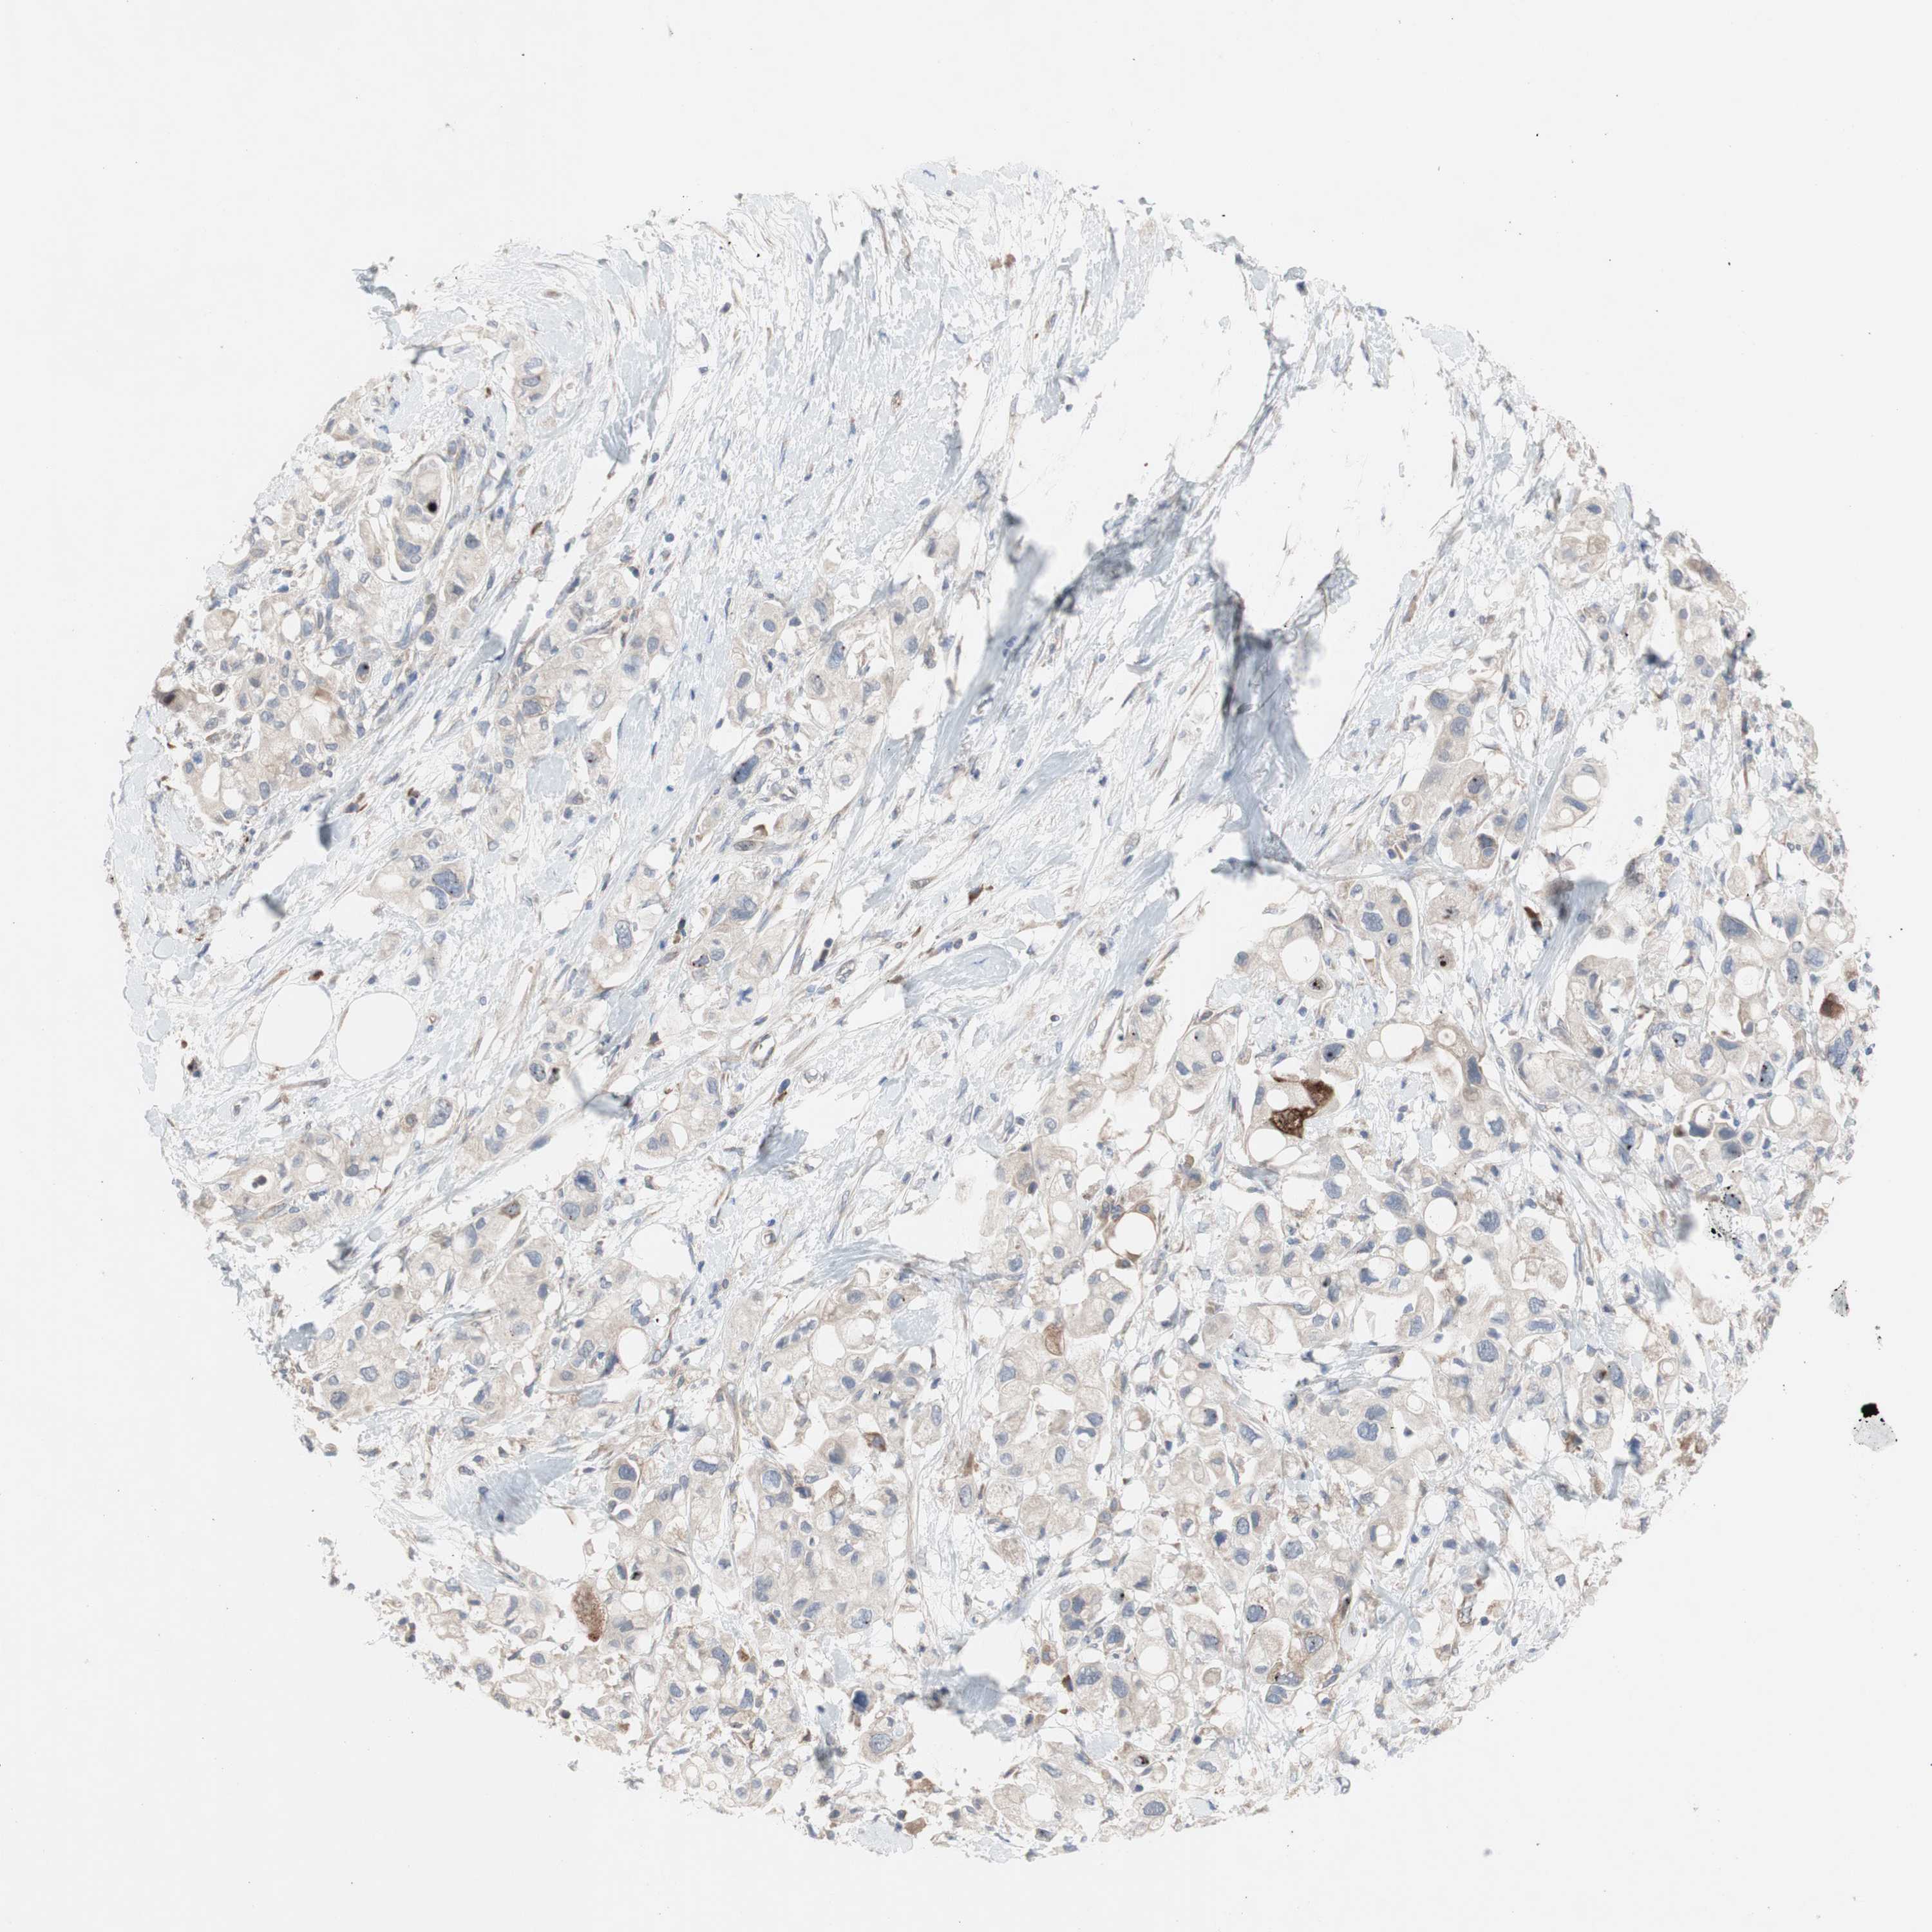

PANCREATIC CANCER - Protein expressioni

A mouse-over function shows sample information and annotation data. Click on an image to view it in a full screen mode. Samples can be filtered based on level of antibody staining by selecting one or several of the following categories: high, medium, low and not detected. The assay and annotation is described here.

Note that samples used for immunohistochemistry by the Human Protein Atlas do not correspond to samples in the TCGA dataset.

Antibody stainingi

Antibody staining in the annotated cell types in the current human tissue is reported as not detected, low, medium, or high, based on conventional immunohistochemistry profiling in selected tissues. This score is based on the combination of the staining intensity and fraction of stained cells.

Each image is clickable and will lead to virtual microscopy that enables deeper exploration of all samples and also displays staining intensity scores, fraction scores and subcellular localization as well as patient and tissue information for each sample.

Antibody HPA009295

Staining

High

Medium

Low

Not detected

Intensity

Strong

Moderate

Weak

Negative

Quantity

>75%

75%-25%

<25%

None

Location

Nuclear

Cytoplasmic/membranous

Cytoplasmic/membranous,nuclear

Adenocarcinoma, NOS